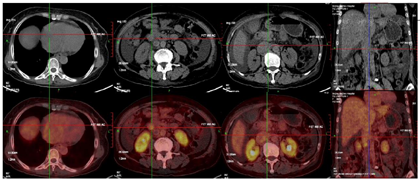

为进一步明确右心房占位性质,行18F-FDG PET/CT显像示(图1):右心房明显增大,其内靠下方半部分心腔内密度不均匀减低灶,大小约8.0cm×6.9cm×5.2cm,该病灶边缘轻度放射性摄取增高,最大标准摄取值(Maximum standardized uptake value,SUVmax)为3.9。下腔静脉自盆腔至右心房入口管径逐渐增粗,最大径4.2cm,腔内见偏心密度增高影,于胰头层面下腔静脉内见不均匀放射性摄取增高,SUVmax 4.3;右下腹下腔静脉在右肾肾门层面放射性摄取增高,SUVmax 7.0,双侧髂静脉血管明显增粗,左侧为著。

诊断:下腔静脉至右心房软组织肿块,恶性病变可能性大。